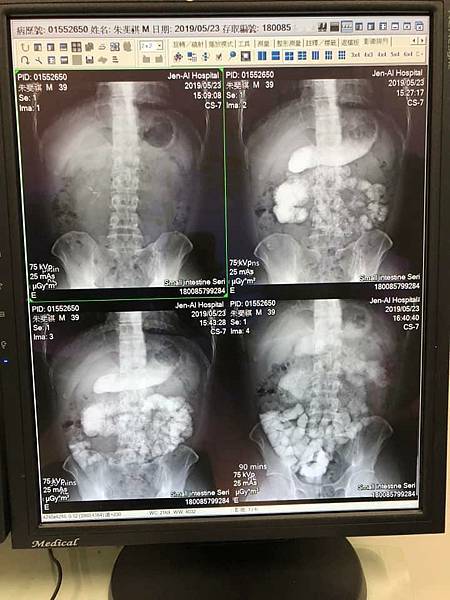

(那時候X光片 我的腸子全部塞住了 )

( 那時候回診追蹤的時後。每一次都要喝這個顯影劑

不知道你們有沒有喝過。超級奇怪的味道